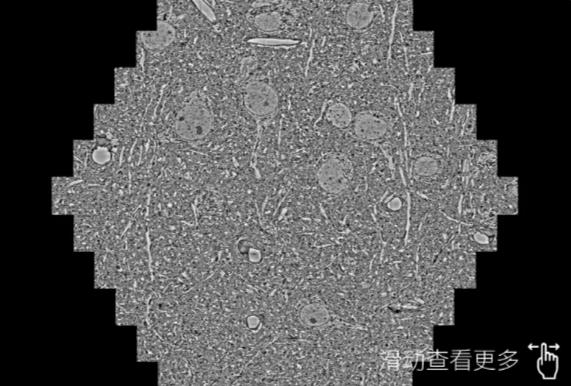

鼠脑切片。左图使用昌邑蔡司昌邑扫描电镜MultiSEM706对165μmx143pm面积区域成像,耗时仅需1.5秒。右图为鼠脑切片中30μm区域放大效果。样品由芝加哥大学B.Kasthuri提供。

使用蔡司高速昌邑扫描电镜MultiSEM对1mm²人脑皮层组织进行高分辨成像,并对其中的各种细胞结构进行三维重构分析。左图展示了2x3mm²组织平面中锥体神经元的三维重构效果。右图显示了局部体积神经元三维重构。图像由哈佛大学chtman实验室提供,渲染图由D. Berger 制作。